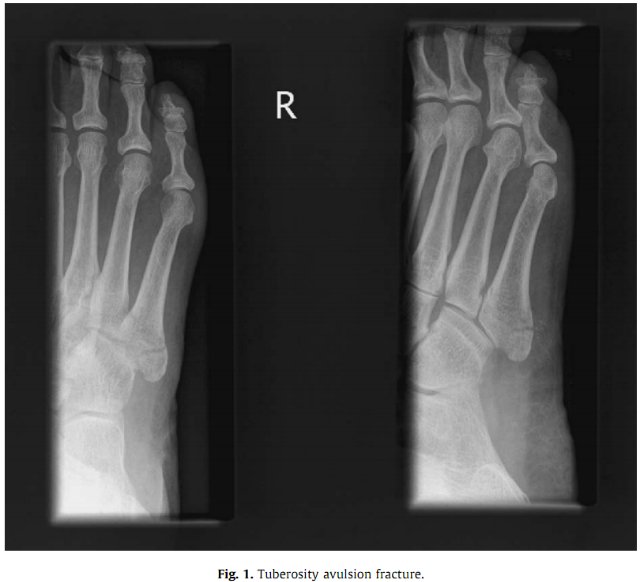

- Человека нужно отвезти в больницу, где ему сделают рентген, чтобы понять, какая кость повреждена, и какова степень тяжести травмы.

Итак, нужно обратиться к травматологу. Но если имеет место быть открытая травма, то потребуется помощь хирурга. Перечислим основные направления и важные моменты, которые включает в себя лечение:

- Обязательно наблюдение врача. Периодически будут делаться рентгенологические снимки, по которым специалист будет оценивать ситуацию и характер сращивания. Вероятно, будут назначены процедуры физиотерапии или особые упражнения.